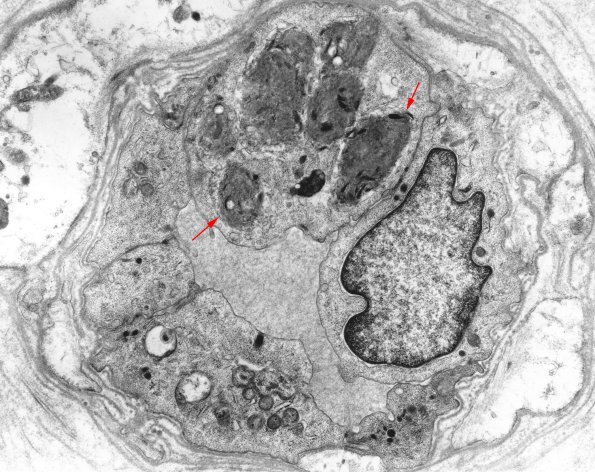

Ultrastructural appearance of an endoneurial venule containing inclusions (arrows). (Image thanks to JM Bilbao) (electron micrograph)